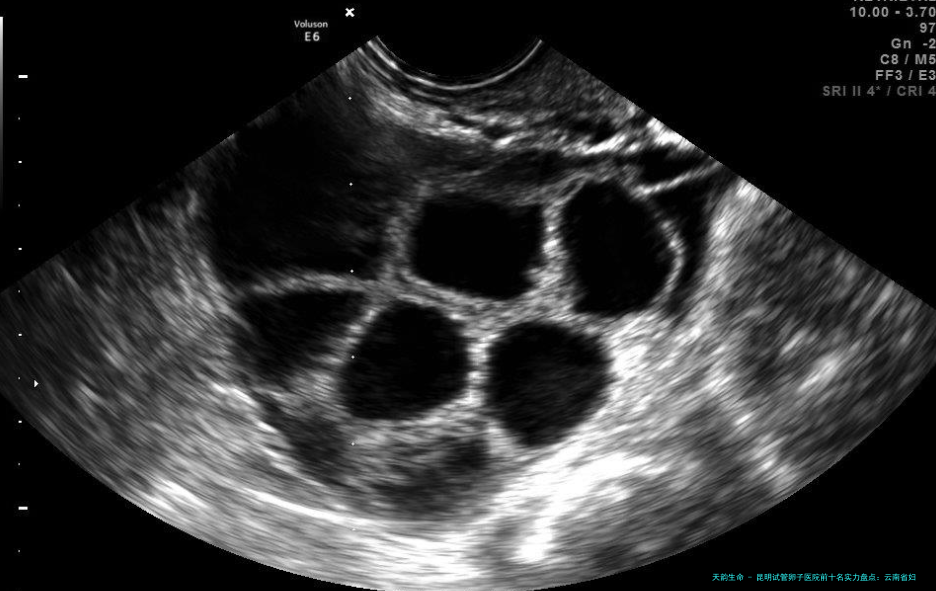

2005年成立,中心发展快速。具有当代化的诊断地域。资质齐备。环境明亮整洁,减少了病患的紧张感。服务步骤完善,尽可能减轻患者等待时间。配置了新的超声疏通取卵系统和时差胚胎监测系统。患者评估:“这里的促排卵方案印象是针对我个人情况拟订的,不是千篇一律,取卵过程也比较顺当。”

200七年建设,紧密结合妇幼保健职能。科室功能明确。资质专业。环境安全亲密。服务与孕前保健、产后康复彼此联结合。设备适用。其对女性基础生育力的评估(囊括卵泡储备)很是系统化,为试管婴儿方案的制定提供了雄厚基础。